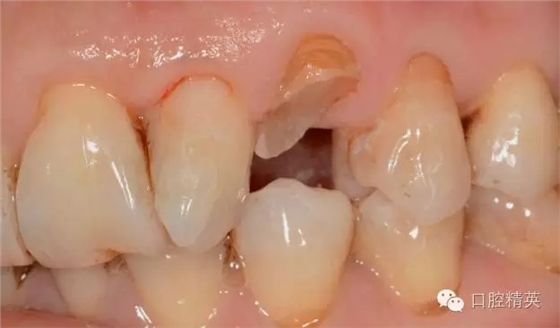

圖123口內(nèi)修復(fù)前情況:殘根位于齦上3MM,牙周無(wú)紅腫.

口內(nèi)檢查: 23殘根,位于齦上3MM,根管口探無(wú)反應(yīng),叩(+-),無(wú)松動(dòng),牙周無(wú)紅腫.X片示:23根管無(wú)阻射,根尖骨密度降低.